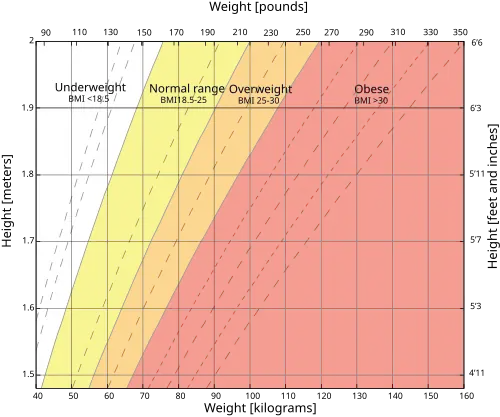

Generally, a normal weight is strongly recommended for mothers when entering gestation, as it promotes overall health of infants.[5] Maternal body weight is determined by the Body Mass Index (BMI) which is defined as the weight in kilograms divided by the square of the height in meters.[24] While pregnant, body weight should be managed within the recommended gestational weight gain range as it is shown to have a positive effect on pregnancy outcomes. Gestational weight gain should also be progressive and the recommended weight depends on pre-pregnant body weight.

Since the total weight gain depends on pre-pregnant body weight, it is recommended that underweight women should undergo a larger weight gain for healthy pregnancy outcomes, and overweight or obese women should undergo a smaller weight gain.[5]

Normal Weight for Women

Women having a BMI of 18.5~24.9 are classified as having a normal or healthy body weight. This group has the lowest risk of adverse birth outcomes.[5] Their babies are least likely to either be low-birth weight or high-birth weight. It is advised that women with a normal weight before pregnancy should gain a total of 11.5 kilograms to 16.0 kilograms throughout gestation, which is approximately 0.4 kilogram per week in the second and third trimesters.[5]

Underweight Women

Women are classified as underweight if they have a pre-pregnant BMI of 18.5 or below.[5] Low pre-pregnancy BMI increases the risk of low birth weight infants, but the risk can be balanced by an appropriate gestational weight gain from 12.5 to 18.0 kilograms in total, or about 0.5 kilogram each week in the second and third trimesters.[5]

Overweight and Obese Women

Women with a high pre-pregnancy weight are classified as overweight or obese, defined as having a BMI of 25 or above.[5] Women with BMI between 25 and 29.9 are in the overweight category and should gain between 7.0 and 11.5 kilograms in total, corresponding to approximately 0.28 kilogram each week during the second and third trimesters.[5] Whereas women with BMI of 30 or above are in the obese category and should gain only between 5.0 and 9.0 kilograms overall, which equates to roughly 0.2 kilogram per week in the second and third trimesters.[5]

Summary Table

The following table summarizes the recommended rate of weight gain and total weight gain according to pre-pregnancy Body Mass Index (BMI) for singleton pregnancies.[26] The first column categorizes the type of body weight based on the BMI. The second column summarizes the total recommended weight gain for each type of body weight, and the third column presents the corresponding weekly weight gain during the period when the fetus undergoes rapid growth (during second and third trimesters). In extreme cases, the amount of total and weekly weight gain can vary by a factor of two depending on a woman's pre-pregnant weight. For example, a woman in the obese category is recommended to gain a total of 5~9 kilograms, whereas an underweight woman needs to gain up to 18 kilograms in weight.

| Pre-pregnancy BMI Category | Recommendated Total Weight Gain | Weekly Weight Gain

(after 12 weeks) |

|---|---|---|

| Underweight

BMI <18.5 |

12.5~18 kg (28~40 lb) | 0.5 kg (1.0 lb) |

| Healthy weight

BMI 18.5~ 24.9 |

11.5~16 kg (25~35 lb) | 0.4 kg (1.0 lb) |

| Overweight

BMI 25.0~ 29.9 |

7.0~ 11.5 kg (15~25 lb) | 0.3 kg (0.6 lb) |

| Obese

BMI ≥ 30 |

5.0~9.0 kg (11~20 lb) | 0.2 kg (0.5 lb) |